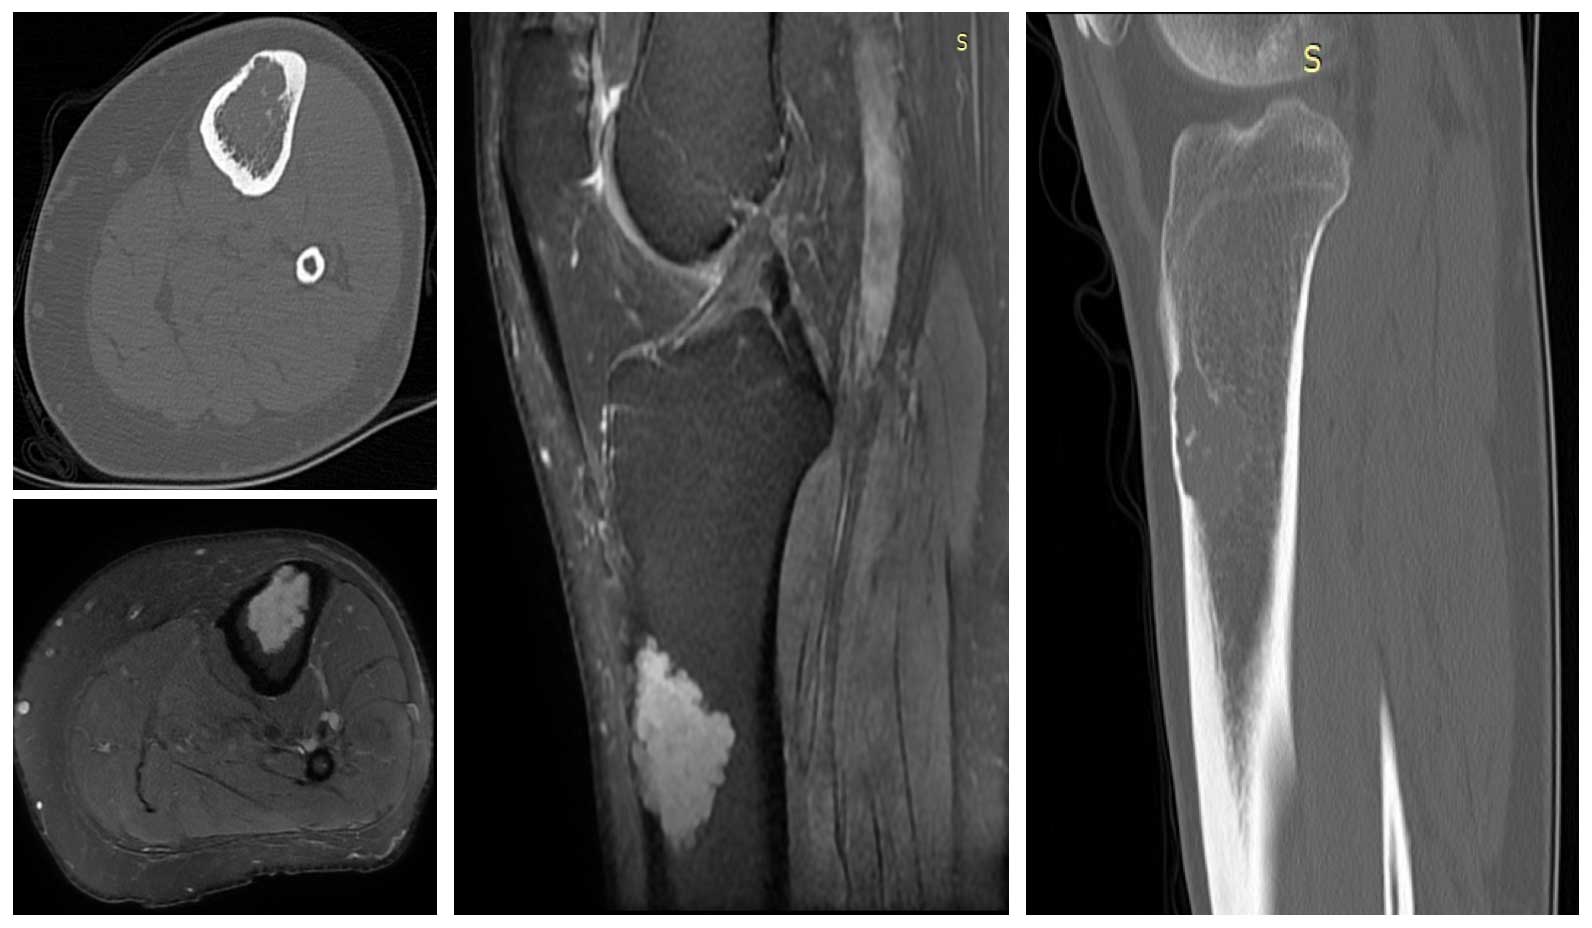

Ameliyat Öncesi: Tomografide kortekste incelme ve kıkırdak dokusu, MR’da tümörün düzensiz sınırları görülmekte.